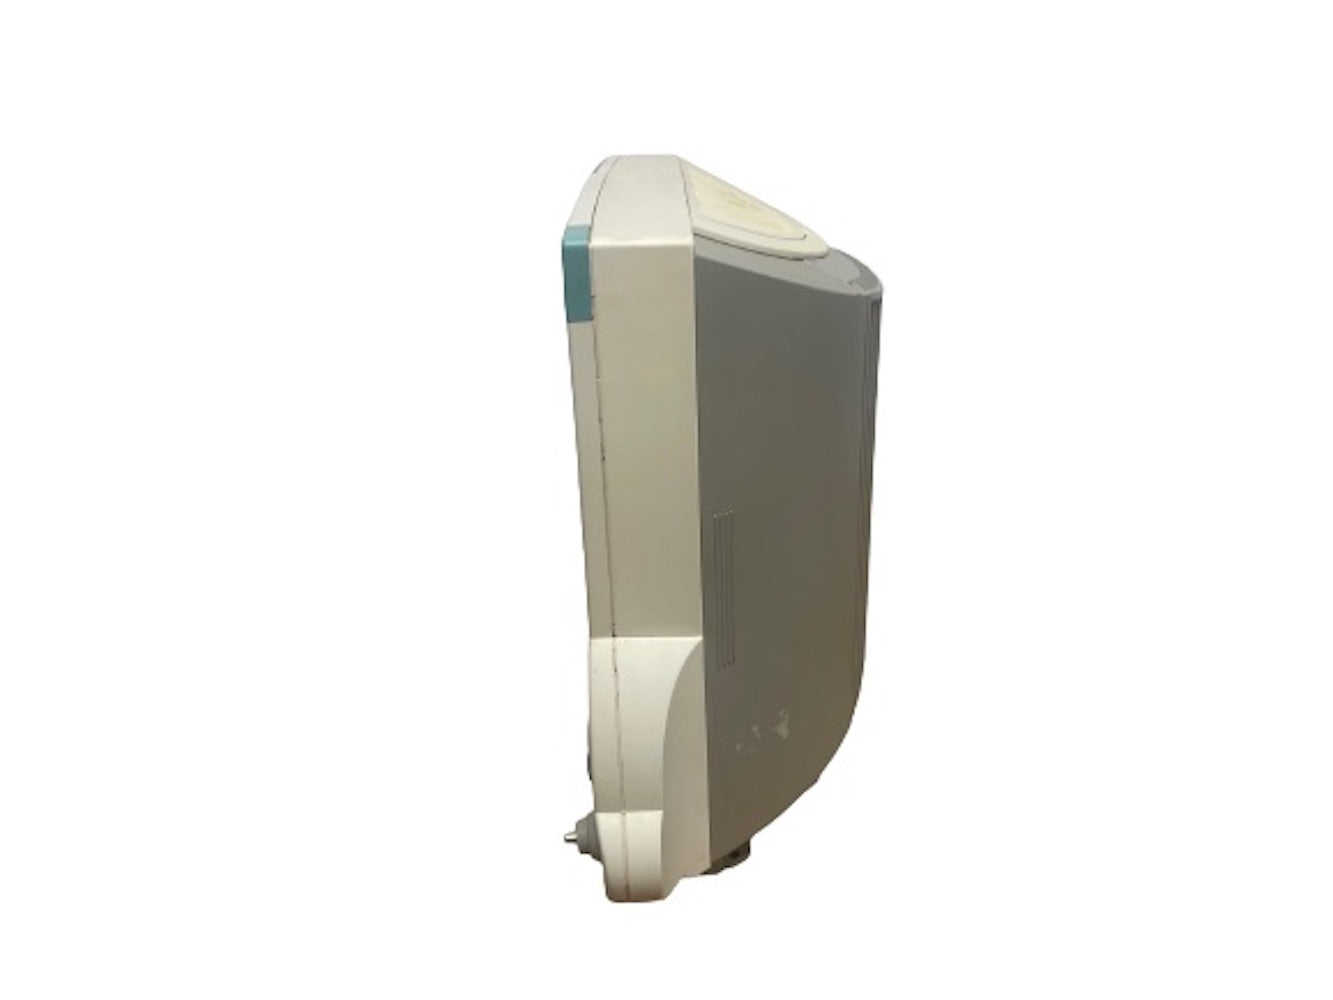

DIAGNOSTIC ULTRASOUND MACHINES FOR SALE

DIAGNOSTIC ULTRASOUND MACHINES FOR SALE

Philips iU22 - A Cart, 3D/4D Ultrasound

Sale price$ 21,585.66